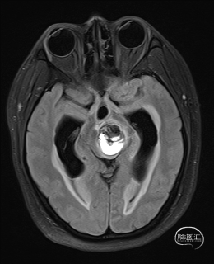

术前MRI检查

术前MRI检查提示左侧丘脑中脑海绵状血管瘤并卒中,梗阻性脑积水;

根据MRI及DTI显示,只有在丘脑与上丘之间的点(dot)进入病变才可能在切除病变时最大程度保护神经功能,由于上述原因,该“点”在术中显露极其困难,虽有导航指引,电生理监测的条件下,对术者的耐心、技术、经验及体能依然是极大的挑战;

从后方有POPPEN入路、Krause入路等,但是因为病变并未充分向松果体区、大脑大静脉后方突出,有大脑大静脉复合体的阻挡,POPPEN入路有较大的难度显露及切除病变,残留的可能性比较大;传统显微镜下进行的幕下小脑上入路在病变的显露及切除上依然有较大的难度。

综上,病变位于左侧丘脑及中脑,传统的手术入路或者显微手术方法有极大的难度和风险;